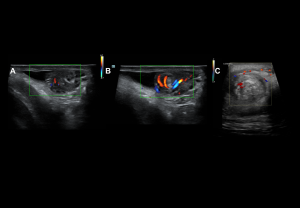

Inflammatory Disorders

Epididymo-orchitis

The most common cause of acute testicular pain in adults.

- Clinical findings: tender enlarged testis, scrotal wall thickening, erythema, fever, positive Prehn’s sign, preserved cremasteric reflex.

- Grey-scale: Enlarged heterogeneous epididymis, testicular enlargement with heterogeneous hypoechogenicity, reactive hydrocele.

- Doppler: Diffuse hyperaemia, low-resistance arterial flow (RI: epididymis <0.7, testis <0.5).